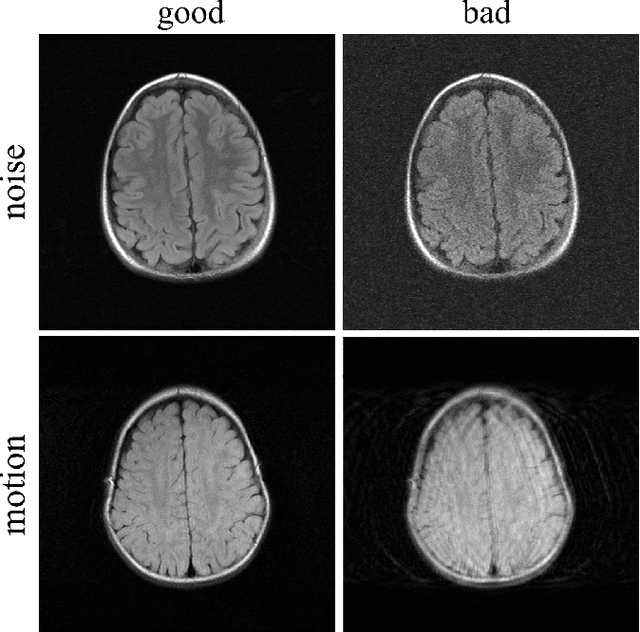

In clinical practice MR images are often first seen by radiologists long after the scan. If image quality is inadequate either patients have to return for an additional scan, or a suboptimal interpretation is rendered. An automatic image quality assessment (IQA) would enable real-time remediation. Existing IQA works for MRI give only a general quality score, agnostic to the cause of and solution to low-quality scans. Furthermore, radiologists' image quality requirements vary with the scan type and diagnostic task. Therefore, the same score may have different implications for different scans. We propose a framework with multi-task CNN model trained with calibrated labels and inferenced with image rulers. Labels calibrated by human inputs follow a well-defined and efficient labeling task. Image rulers address varying quality standards and provide a concrete way of interpreting raw scores from the CNN. The model supports assessments of two of the most common artifacts in MRI: noise and motion. It achieves accuracies of around 90%, 6% better than the best previous method examined, and 3% better than human experts on noise assessment. Our experiments show that label calibration, image rulers, and multi-task training improve the model's performance and generalizability.